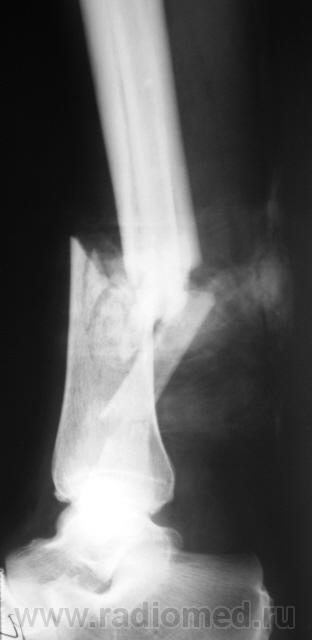

Травма. Вот, такой переломчик...

Травма.  Произведена рентгенография в стандартных проекциях.

Наверное, открытый?

Нет. Закрытый.

Здравствуйте, уважаемый Валентин Львович! Очень похож на "бамперный перелом". У меня вопрос - а почему снимки без шины? Ведь пациенту наверняка было больно при проведении исследования в двух проекциях.

Чегото на боковом структура кости не странная? Как будто в области перелома есть еще дополнительное тенеобразование..     Мягкие ткани?